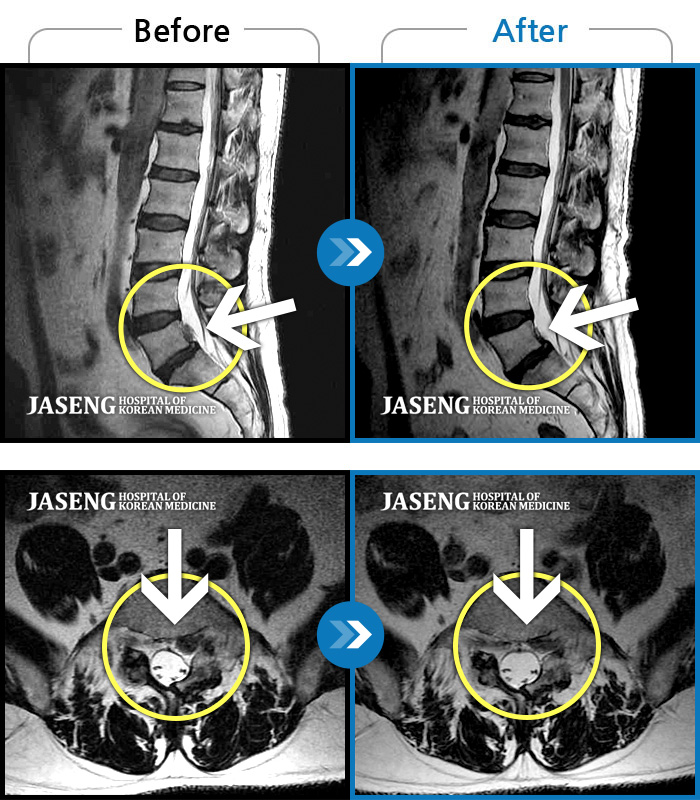

허리디스크

보라매 · 빈상은 원장

좌측 허리부터 고관절 통증이 심하고 다리까지 저려서 허리를 똑바로 펴기 힘들어요.

촬영시기

2020.07.27 ~ 2023.01.20

2023.11.24

조회수 468